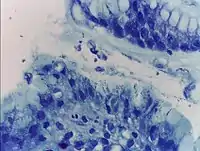

Гистологический метод

Первым методом, который стали использовать для диагностики геликобактерной инфекции, является гистологический метод. Материалом исследования являются клетки тканей, полученных с помощью биопсии, производимой во время эндоскопического обследования желудка и двенадцатиперстной кишки. Специфичность гистологического метода может достигать 100%, а чувствительность — 91-93%, ввиду того, что бактерии неравномерно распределены по слизистой оболочке желудка: взятие производится из мест с максимально выраженной гиперемией и отёком, при этом взятие из дна язв и эрозий, а также из их краев, является ошибкой, поскольку в них нет эпителиальных клеток, необходимых для колонизации бактерий. Кроме того, приём антибиотиков и ингибиторов протонной помпы может трансформировать бактерии из спиралевидной формы в кокковую, которую невозможно выявить с помощью обычной микроскопии.[52]